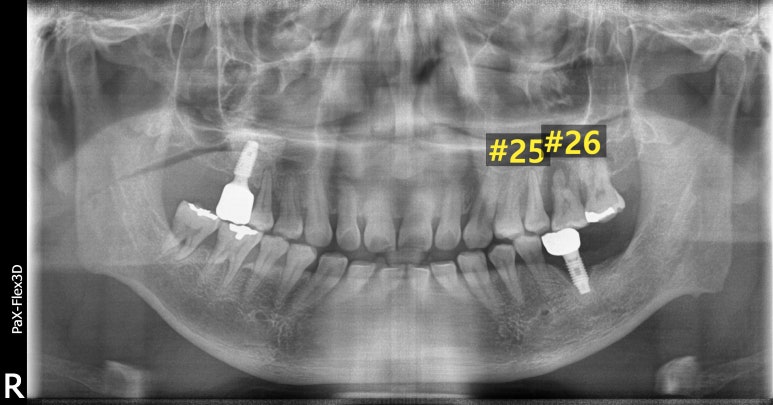

임플란트 1차 수술 후

2022-09-16

발치 4개월 후 임플란트 1차 수술을 진행해 픽스처를 식립했습니다.

이렇게 임플란트 수술을 마치고 환자분 잇몸 상태를 고려해 지속적인 잇몸치료도 권유 드렸습니다.

이제 잇몸뼈와 임플란트가 잘 유착되었는지 확인 후 수치가 잘 나왔다면

치아 역할을 하는 크라운 본을 뜨고 크라운을 제작해 얹어주는 작업만 남았는데요.

임플란트 수술 전후

(전) 2022-04-28 (후) 2023-04-06